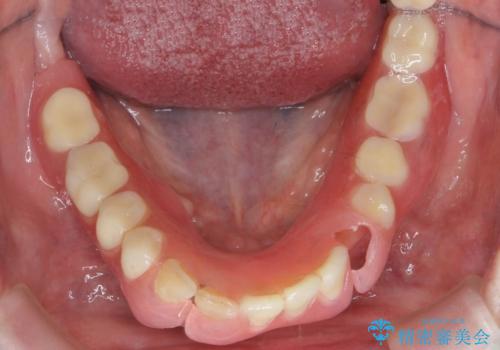

セラミック・インプラント治療を含む包括歯周病治療

できる限り口の中を綺麗にしたい。